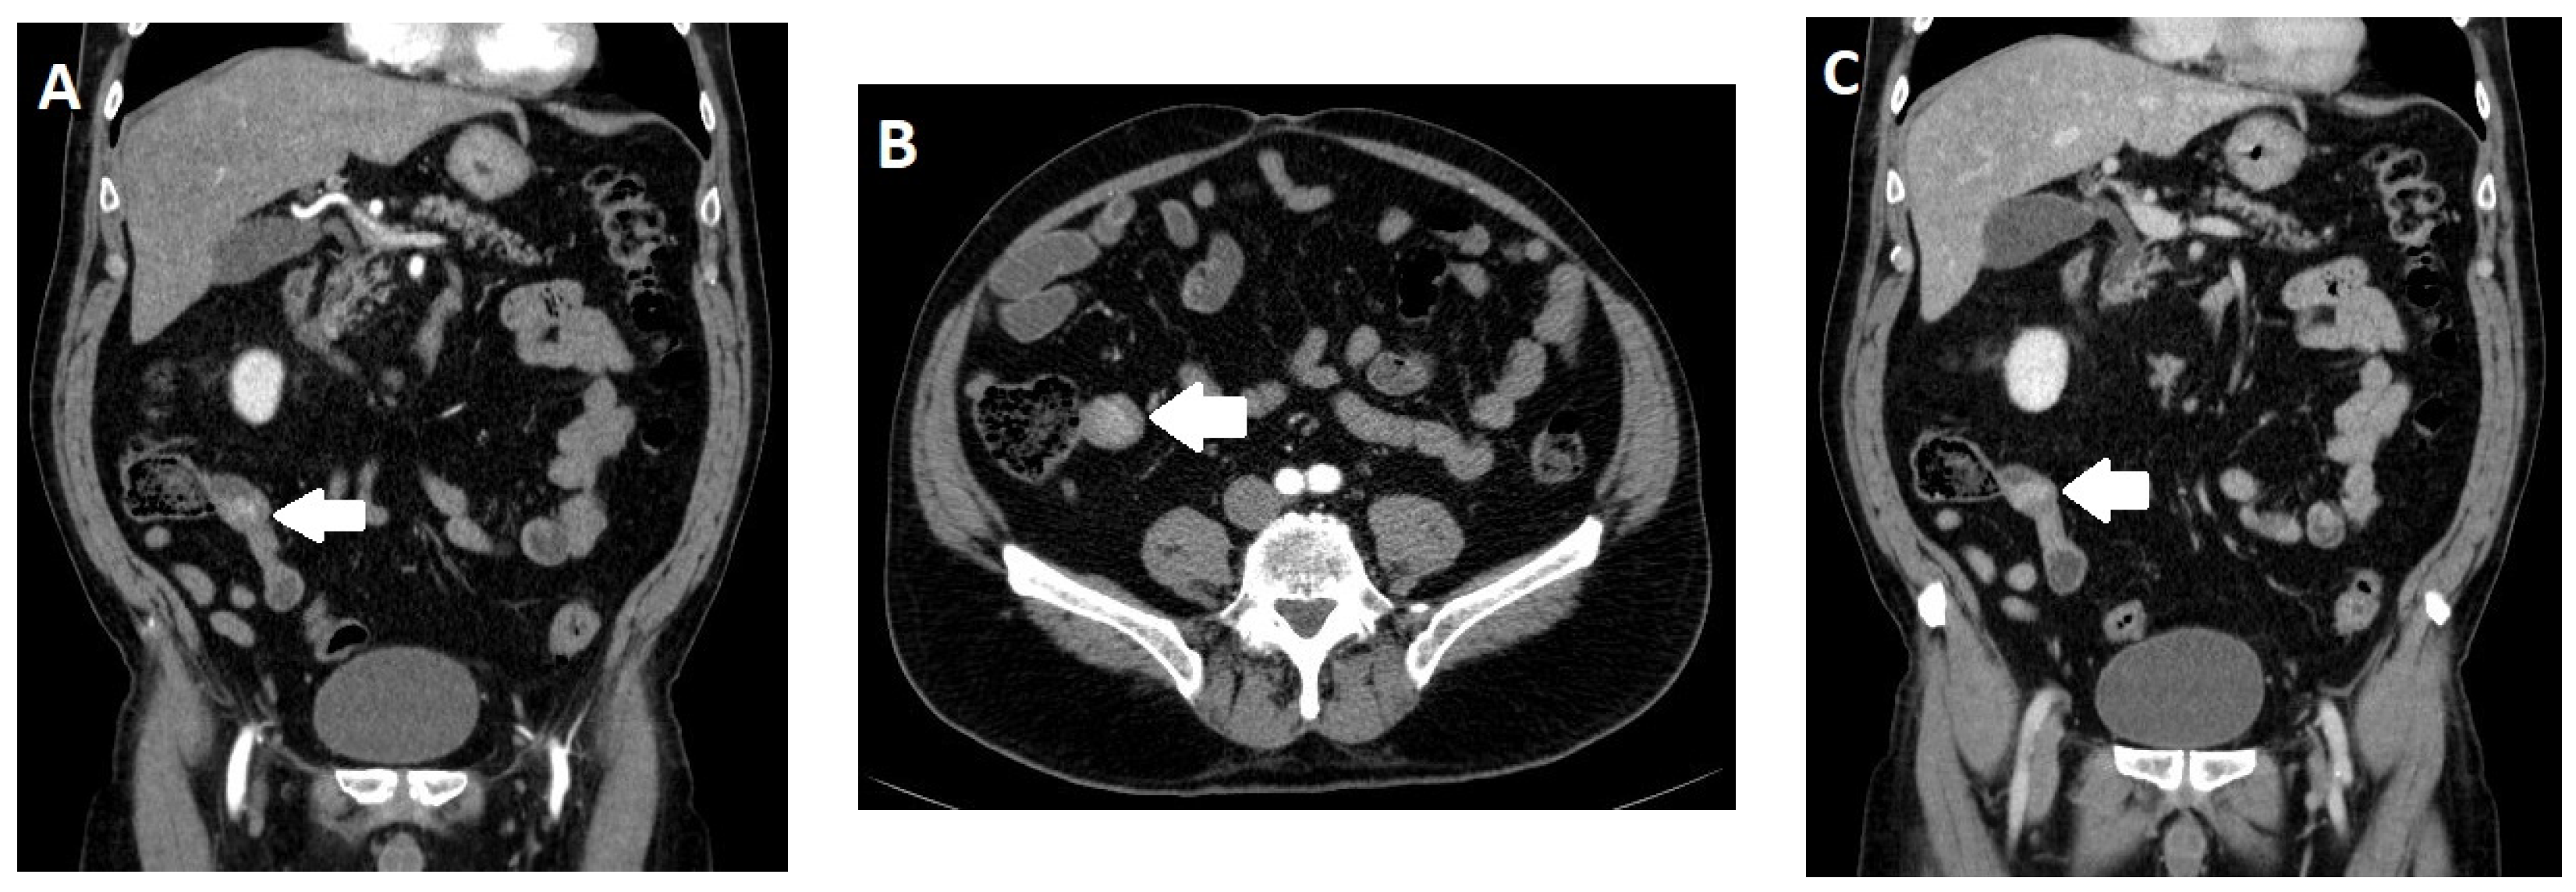

2.4. Imaging

- Morani, A.C.; Gupta, S.; Elsayes, K.M.; Mubarak, A.I.; Khalaf, A.M.; Bhosale, P.R.; Sun, J.; Jensen, C.T.; Kundra, V. Performance of Multidetector Computed Tomography and Negative Versus Positive Enteric Contrast for Evaluation of Gastrointestinal Neuroendocrine Neoplasms. J. Comput. Assist. Tomogr. 2022, 46, 333–343. [Google Scholar] [CrossRef]

- Pilleul, F.; Penigaud, M.; Milot, L.; Saurin, J.C.; Chayvialle, J.A.; Valette, P.J. Possible small-bowel neoplasms: Contrast-enhanced and water-enhanced multidetector CT enteroclysis. Radiology 2006, 241, 796–801. [Google Scholar] [CrossRef]

- Soyer, P.; Dohan, A.; Eveno, C.; Dray, X.; Hamzi, L.; Hoeffel, C.; Kaci, R.; Boudiaf, M. Carcinoid tumors of the small-bowel: Evaluation with 64-section CT-enteroclysis. Eur. J. Radiol. 2013, 82, 943–950. [Google Scholar] [CrossRef]

- Dohan, A.; El Fattach, H.; Barat, M.; Guerrache, Y.; Eveno, C.; Dautry, R.; Mule, S.; Boudiaf, M.; Hoeffel, C.; Soyer, P. Neuroendocrine tumors of the small bowel: Evaluation with MR-enterography. Clin. Imaging 2016, 40, 541–547. [Google Scholar] [CrossRef]